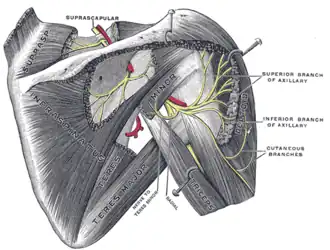

Suprascapular and axillary nerves of right side, seen from behind. (Teres minor is visible at center.)

Suprascapular and axillary nerves of right side, seen from behind. (Teres minor is visible at center.) -